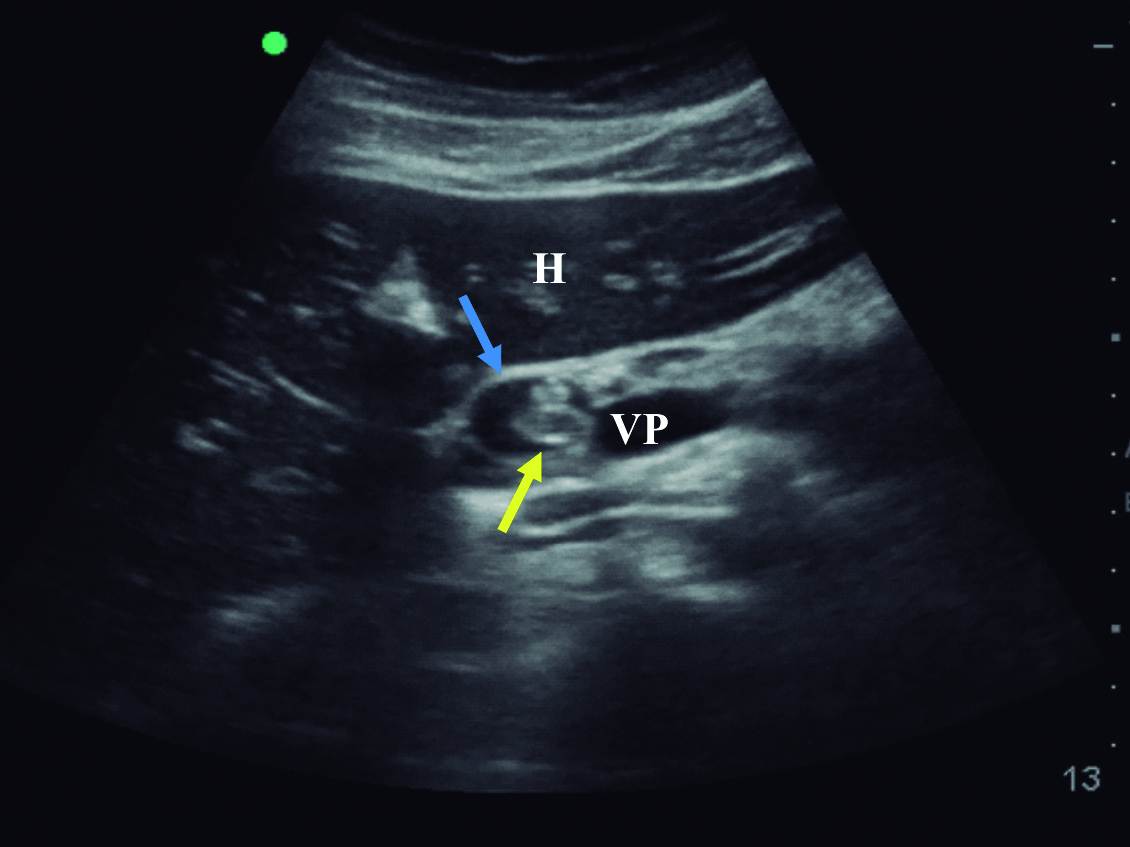

Se interroga a la paciente y refiere haber sido estudiada previamente con una colangiografía por resonancia magnética tres meses previo a la consulta en otro centro hospitalario. En ese momento la vía biliar principal no estaba ocupada. Retrospectivamente se identificaron los parásitos en el tubo digestivo proximal (Fig. 4 y 5).

Figura 4. Resonancia Magnética

a y b) Imágenes en plano coronal potenciadas en T2 sin saturación grasa. A nivel de asas yeyunales proximales se identifican los parásitos como imágenes lineales ligeramente hiperintensas con un área central hipointensa (*).

Figura 5. Colangiografía por Resonancia Magnética - Reconstrucción

Se visualiza vía biliar intra y extrahepática de calibre habitual, sin defectos de relleno.